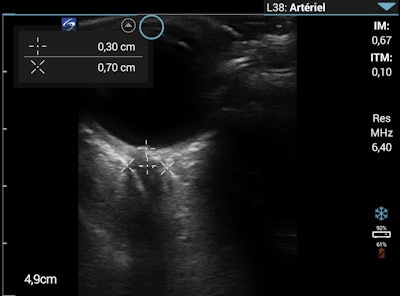

Optic nerve sheath diameter measurement on the morning of day eight. Images courtesy of Wilderness and Environmental Medicine and Dr. Flavia Wipplinger, et al. Licensed under CC BY-NC-ND 4.0.Acute high-altitude illness includes acute mountain sickness, high-altitude pulmonary edema (HAPE), and high-altitude cerebral edema. These illnesses are caused by hypobaric hypoxia and can develop within a few days after ascent to altitudes above 8,200 feet.

That evening in Dingboche, the patient, a physician himself, was alert, oriented, and showed no signs of ataxia with tandem gait. Lung auscultation was normal, with an absence of inspiratory crackles. Lung ultrasound, however, showed one to two B-lines in four of the four lung regions. The ONSD measurement remained unchanged at 6 mm.

At breakfast, he did not have a cough or a fever. He was mildly ataxic with tandem gait but had normal mental status without other neurologic findings. On lung ultrasound, the number of B-lines in all regions had increased compared with the previous evening and the ONSD had increased to 7 mm.